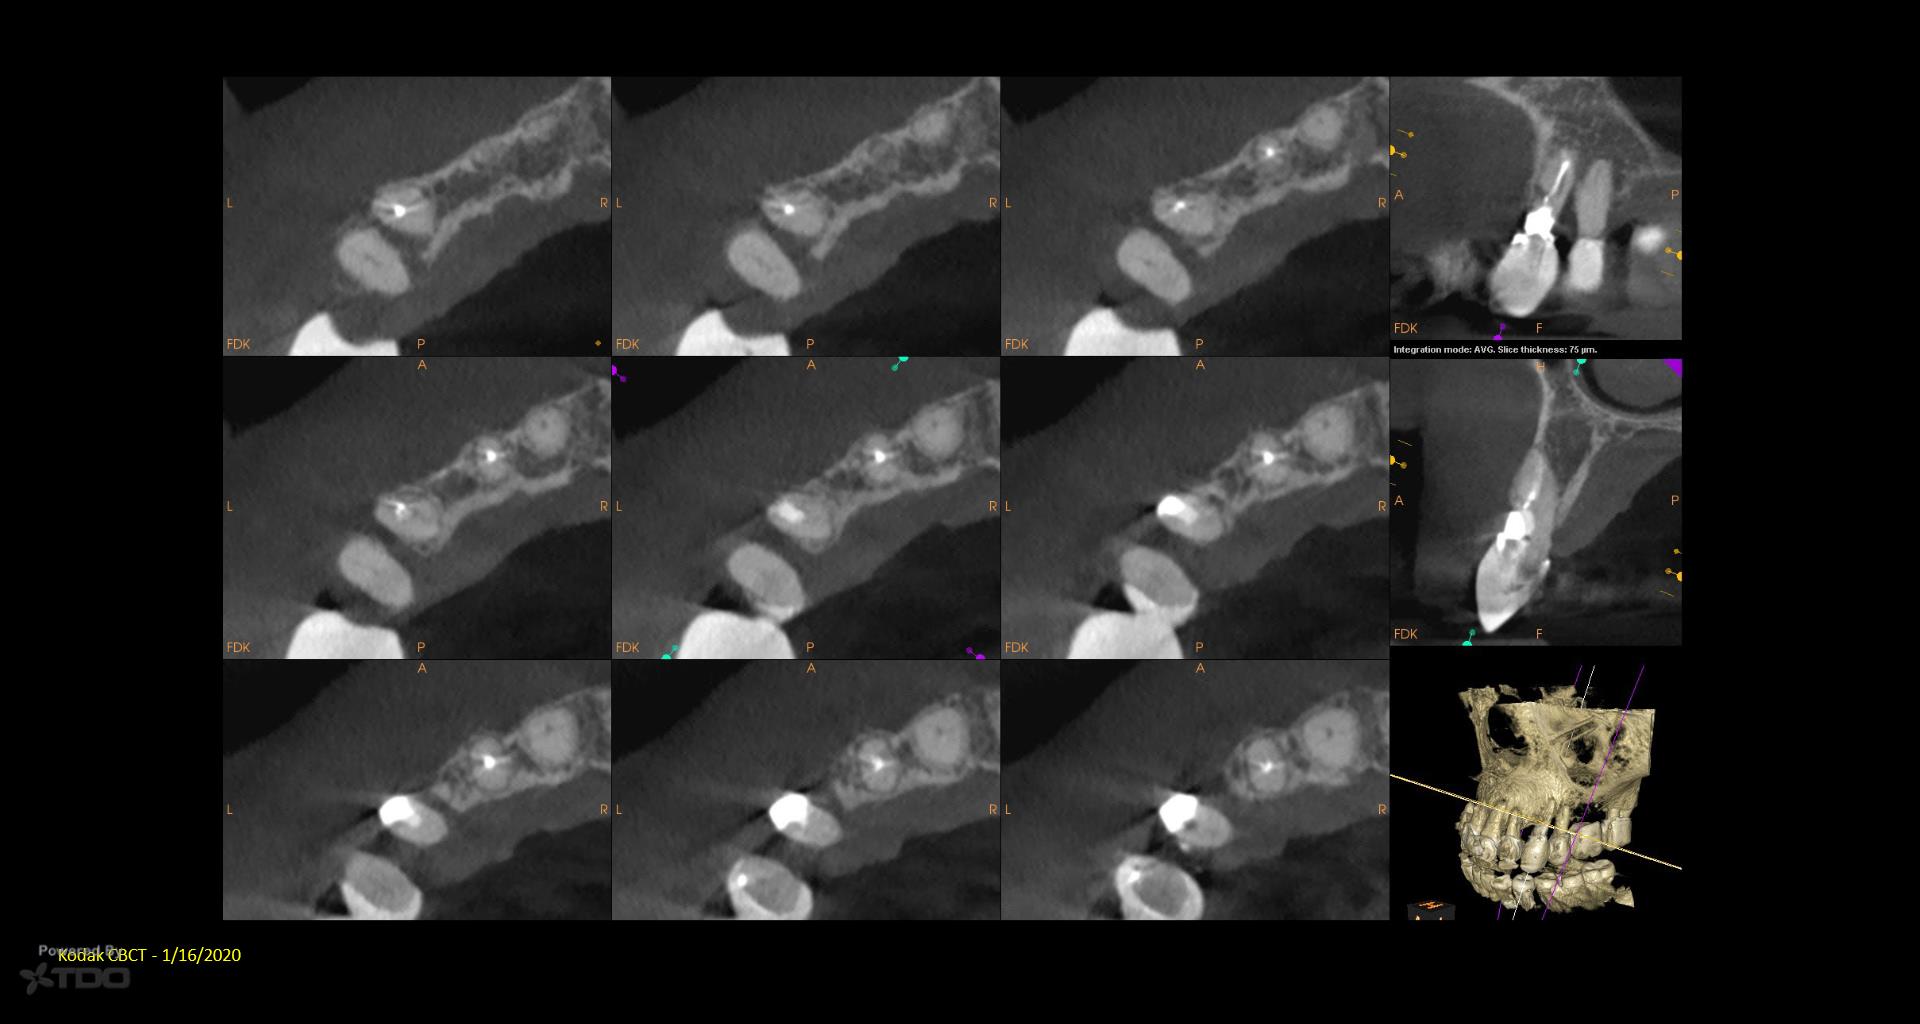

I posted this last month after the consult. There was mixed TDO advice—some said “do it” and others said monitor. Reluctantly, I did it Monday. I couldn’t really address the ECIR that was sub-osseous without removing way too much bone. I just hit it with the Pear Diamond as well as I could. Time will tell if it was a fool’s errand. I video’d the whole thing but don’t have the time to edit it. gbc